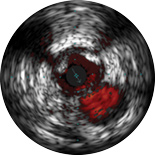

ChromaFlo provides easy assessment of stent apposition, lumen size and more by highlighting blood flow red at the touch of a button. ChromaFlo is available on Philips imaging systems.

Designed to make lumen size and stent apposition instantly recognizable and help identify branches, dissections, thrombus, and plaque distribution in bifurcations. ChromaFlo highlights blood flow red to identify:

No flushing and no special procedures are required during imaging. Simply activate ChromaFlo with a click.

ChromaFlo works with the Philips Eagle Eye Platinum digital IVUS catheters.